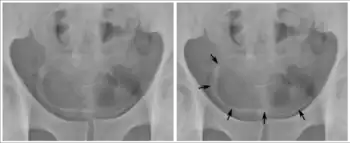

Calcifications on bladder wall caused by urinary schistosomiasis

Cystitis refers to infection or inflammation of the bladder. It commonly occurs as part of a urinary tract infection.[23] In adults, it is more common in women than men, owing to a shorter urethra. It is common in males during childhood, and in older men where an enlarged prostate may cause urinary retention.[23] Other risk factors include other causes of blockage or narrowing, such as prostate cancer or the presence of vesico-ureteric reflux; the presence of outside structures in the urinary tract, such as urinary catheters; and neurologic problems that make passing urine difficult.[23] Infections that involve the bladder can cause pain in the lower abdomen (above the pubic symphysis, so called "suprapubic" pain), particularly before and after passing urine, and a desire to pass urine frequently and with little warning (urinary urgency).[23] Infections are usually due to bacteria, of which the most common is E coli.[23]